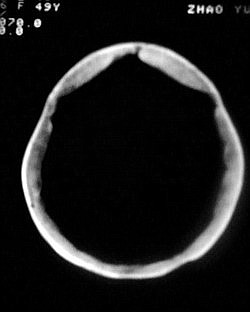

患者/49y/ 女/4年前有脑梗, 现因右侧肢体无力来院做ct扫描 ! 老师们看看这骨头有事吗?钙化点是什么原因呀??

1.颅骨对称性、形态规整性增厚,应属发育异常。四叠体池左后侧单发点状钙化,无其他阳性表现,多属正常,不需要过多关注。

2、颅骨形态规整性的增厚,密度增高,有无骨髓方面的疾病,建议骨髓穿刺。

可能为颅骨内板增生症,以额骨多见,常见于女性.多无临床意义.部分病人可有头痛.可找相关资料看看.

2.颅骨内外板广泛性增厚,板障狭窄甚至消失,双侧对称。无明显相应临床症状。考虑“泛发性骨皮质增厚症”。可进一步检查下颌骨及管状骨骨干。(下颌骨骨小梁增多、密集,密度增高亦为本病特点,管状骨骨干皮质向内增厚引起骨皮质厚度增加,骨密度增浓、髓腔狭窄但不消失,骨干周径较少增加)。与石骨症鉴别,后者很少影响颅盖骨和下颌骨,管状骨改变主要累及干骺端和骨骺,而骨干皮质较少增厚,椎体和髂骨翼有特征性表现。

“泛发性骨皮质增厚症,又称骨内膜增生症(endosteal hyperostosis):分为常染色体隐性遗传性疾病(van buchem)和常染色体显性遗传性骨硬化症(worth病)。后者更少见,亦较轻。两者的病理上均为骨内膜 成熟的板状新生骨形成,髓腔变窄。颅骨、颅底骨 、下颌骨,肋骨、四肢骨及骨盆骨、脊柱均可见骨内膜增生,髓腔变窄或消失,但骨外径不加大,骨骺不累及。”

本例的确应该这个病。建议楼主检查病人其他部位有无类似表现,以便确诊。